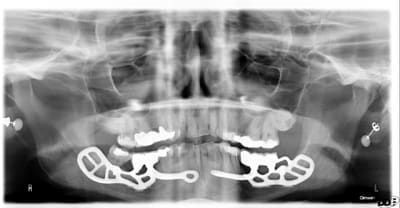

Le dentascan de la mandibule pour que vous compreniez mieux la difficulté...quais impossible de la considérer en cylindres même en déplaçant le NDI vous n avez aucune hauteur exploitable... Même des lame de Likow n y passent pas et les sous périostés sont interdits en Europe

J ai perdu mes deux foutus cylindres et ai dû les remplacer par deux double disk...et changer les deux mono disk du secteur droit

Et oui l implanto basale n est pas non plus un long fleuve tranquille